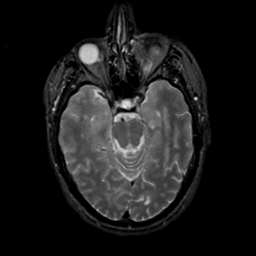

MR Study #20 October 6, 1991 -- Slice #18